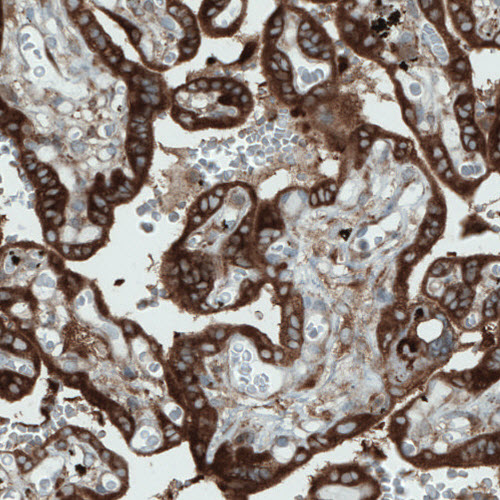

Product information "Anti-DIAPH2, clone CL1111"

Protein function: Could be involved in oogenesis. Involved in the regulation of endosome dynamics. Implicated in a novel signal transduction pathway, in which isoform 3 and CSK are sequentially activated by RHOD to regulate the motility of early endosomes through interactions with the actin cytoskeleton. [The UniProt Consortium] Validated by genetic and standard strategies. Buffer: 40% glycerol and PBS (pH 7.2). 0.02% sodium azide is added as preservative. Highest antigen sequence identity to mouse: 82% and to rat: 33%. Epitope specificity: SLNLSEKEVLDLFEK.

| Application: | IHC, WB |